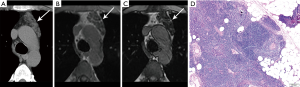

CT plays a major role in the diagnosis and characterization of thymoma. CT imaging has been found to have 88.5% sensitivity and 77% specificity for thymoma, based on a case series of 104 patients with myasthenia gravis (22). On imaging, thymoma may not conform to the shape of normal thymic tissue. Thymoma usually presents as a smoothly-circumscribed, encapsulated soft-tissue density lesion (3) (Figure 1), often homogeneous in enhancement. Calcification may be seen, and is more common in invasive rather than noninvasive (encapsulated) thymomas (23). Areas of necrosis, cystic change, or hemorrhage are less common (3).

Cystic thymomas (Figure 2) and benign thymic cysts may mimic one another, with MRI very useful for differentiating these entities. MRI may identify fibrous internal septae, soft tissue mural nodularity, and enhancement, as well as characterize fluid as simple, proteinaceous, or hemorrhagic. Any foci of hemorrhage would appear T1 hyperintense. Soft tissue components are hypo to iso-intense on T1-weighted images, and hyperintense on T2-weighted sequencing. In addition to MRI’s superiority to CT in discerning soft tissue components and fluid characterization, it may also be helpful in distinguishing local invasion. PET/CT does not have a large role in terms of diagnostic specificity.

Certain morphologic and imaging features can indicate advanced disease (Figure 3). Key findings to identify include mediastinal pleural invasion or pericardial extension and invasion, loss of fat planes between mediastinal vasculature and viscera, and nodal or metastatic lesions. Pleural, pericardial or distant metastases are exceedingly rare in types A and AB thymoma. Local recurrence/spread is estimated to occur in less than 5% of type B1, 11% of type B2, and 18% of type B3 thymomas; distant metastases occur in approximately 3% with types B2 and B3 thymomas (3).

The hallmark of the histological diagnosis of thymoma is the presence of two cell populations, one comprised of epithelial cells and another of immature lymphocytes (Figure 4). However, this classic feature may not be present in many cases due to sampling and histological variation. Immunohistochemical (IHC) stains are very helpful as the thymocyte epithelial cells are positive for keratin, whereas immature lymphocytes are positive for TdT. There must be close co-localization of the two cell populations, as the markers individually are not specific for the diagnosis of thymoma and can be seen in other entities. As an example, TdT positive lymphocytes are present in acute lymphoblastic lymphoma, a common lymphoproliferative disorder of the mediastinum in children and younger adults. The immature (TdT positive) lymphocytes are also seen in metastatic thymoma, a useful diagnostic feature for the diagnosis of thymoma outside of the mediastinum.

On imaging, thymic carcinoma is more likely to be poorly or irregularly marginated and more likely to have internal heterogeneity due to calcification or cystic/necrotic change (Figure 5A). Thymic carcinomas are often associated with pericardial or pulmonary parenchymal invasion (40%), pleural invasion (30%), and vascular invasion (20%) into the superior vena cava or brachiocephalic veins (3). Additionally, a higher proportion, approximately 19–50%, present with distant metastases, most often to bone, liver, lung, and adrenal gland, at time of diagnosis in comparison to thymoma (3). Pericardial effusion, pleural effusion, or enlarged lymph nodes are also more likely with thymic carcinoma than thymoma.

The histological diagnosis of thymic carcinoma is characterized by the clearly malignant features of the epithelial cells and the absence of TdT positive lymphocytes (Figure 5B), in contrast to thymoma.